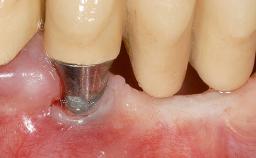

Implant Placement in the Esthetic Zone and Coverage of Multiple Gingival Recessions

This case illustrates use of a modified ‘tunnel’ technique, which has been shown to be highly effective in root coverage procedures. The tunnel technique is used to achieve soft-tissue augmentation across the anterior area, including the planned implant site, using collagen matrix as grafting material. The patient is a 47-year-old woman with high esthetic expectations. Her main concern was the appearance of the anterior teeth and their “elongation”.

Soft Tissue Grafting Staged